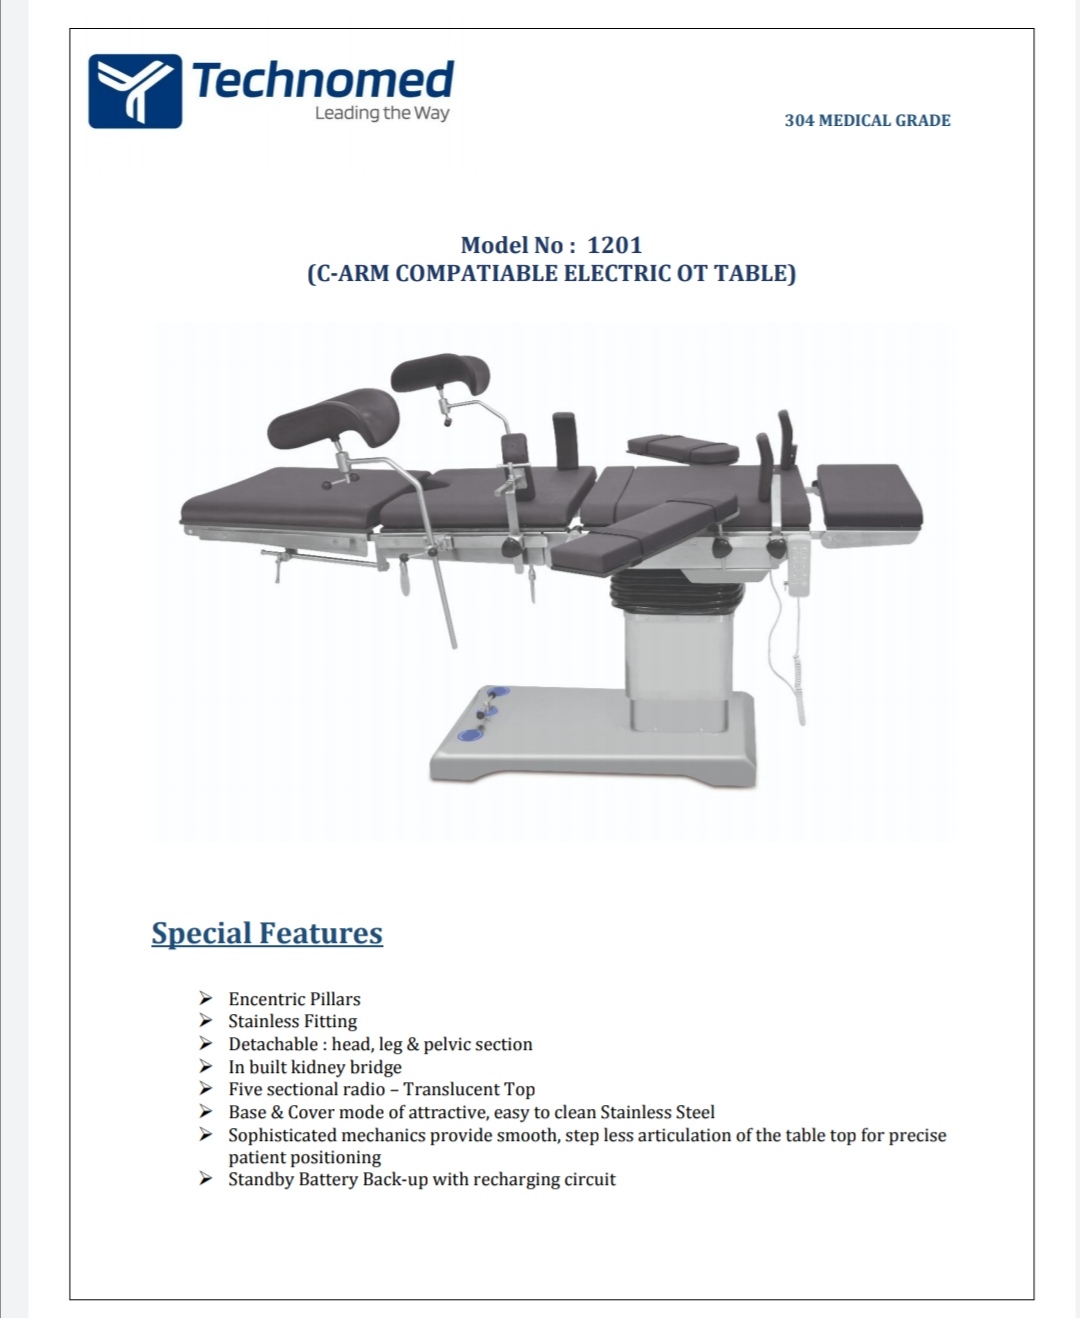

ELECTRIC OT TABLE

ELECTRIC OT TABLE